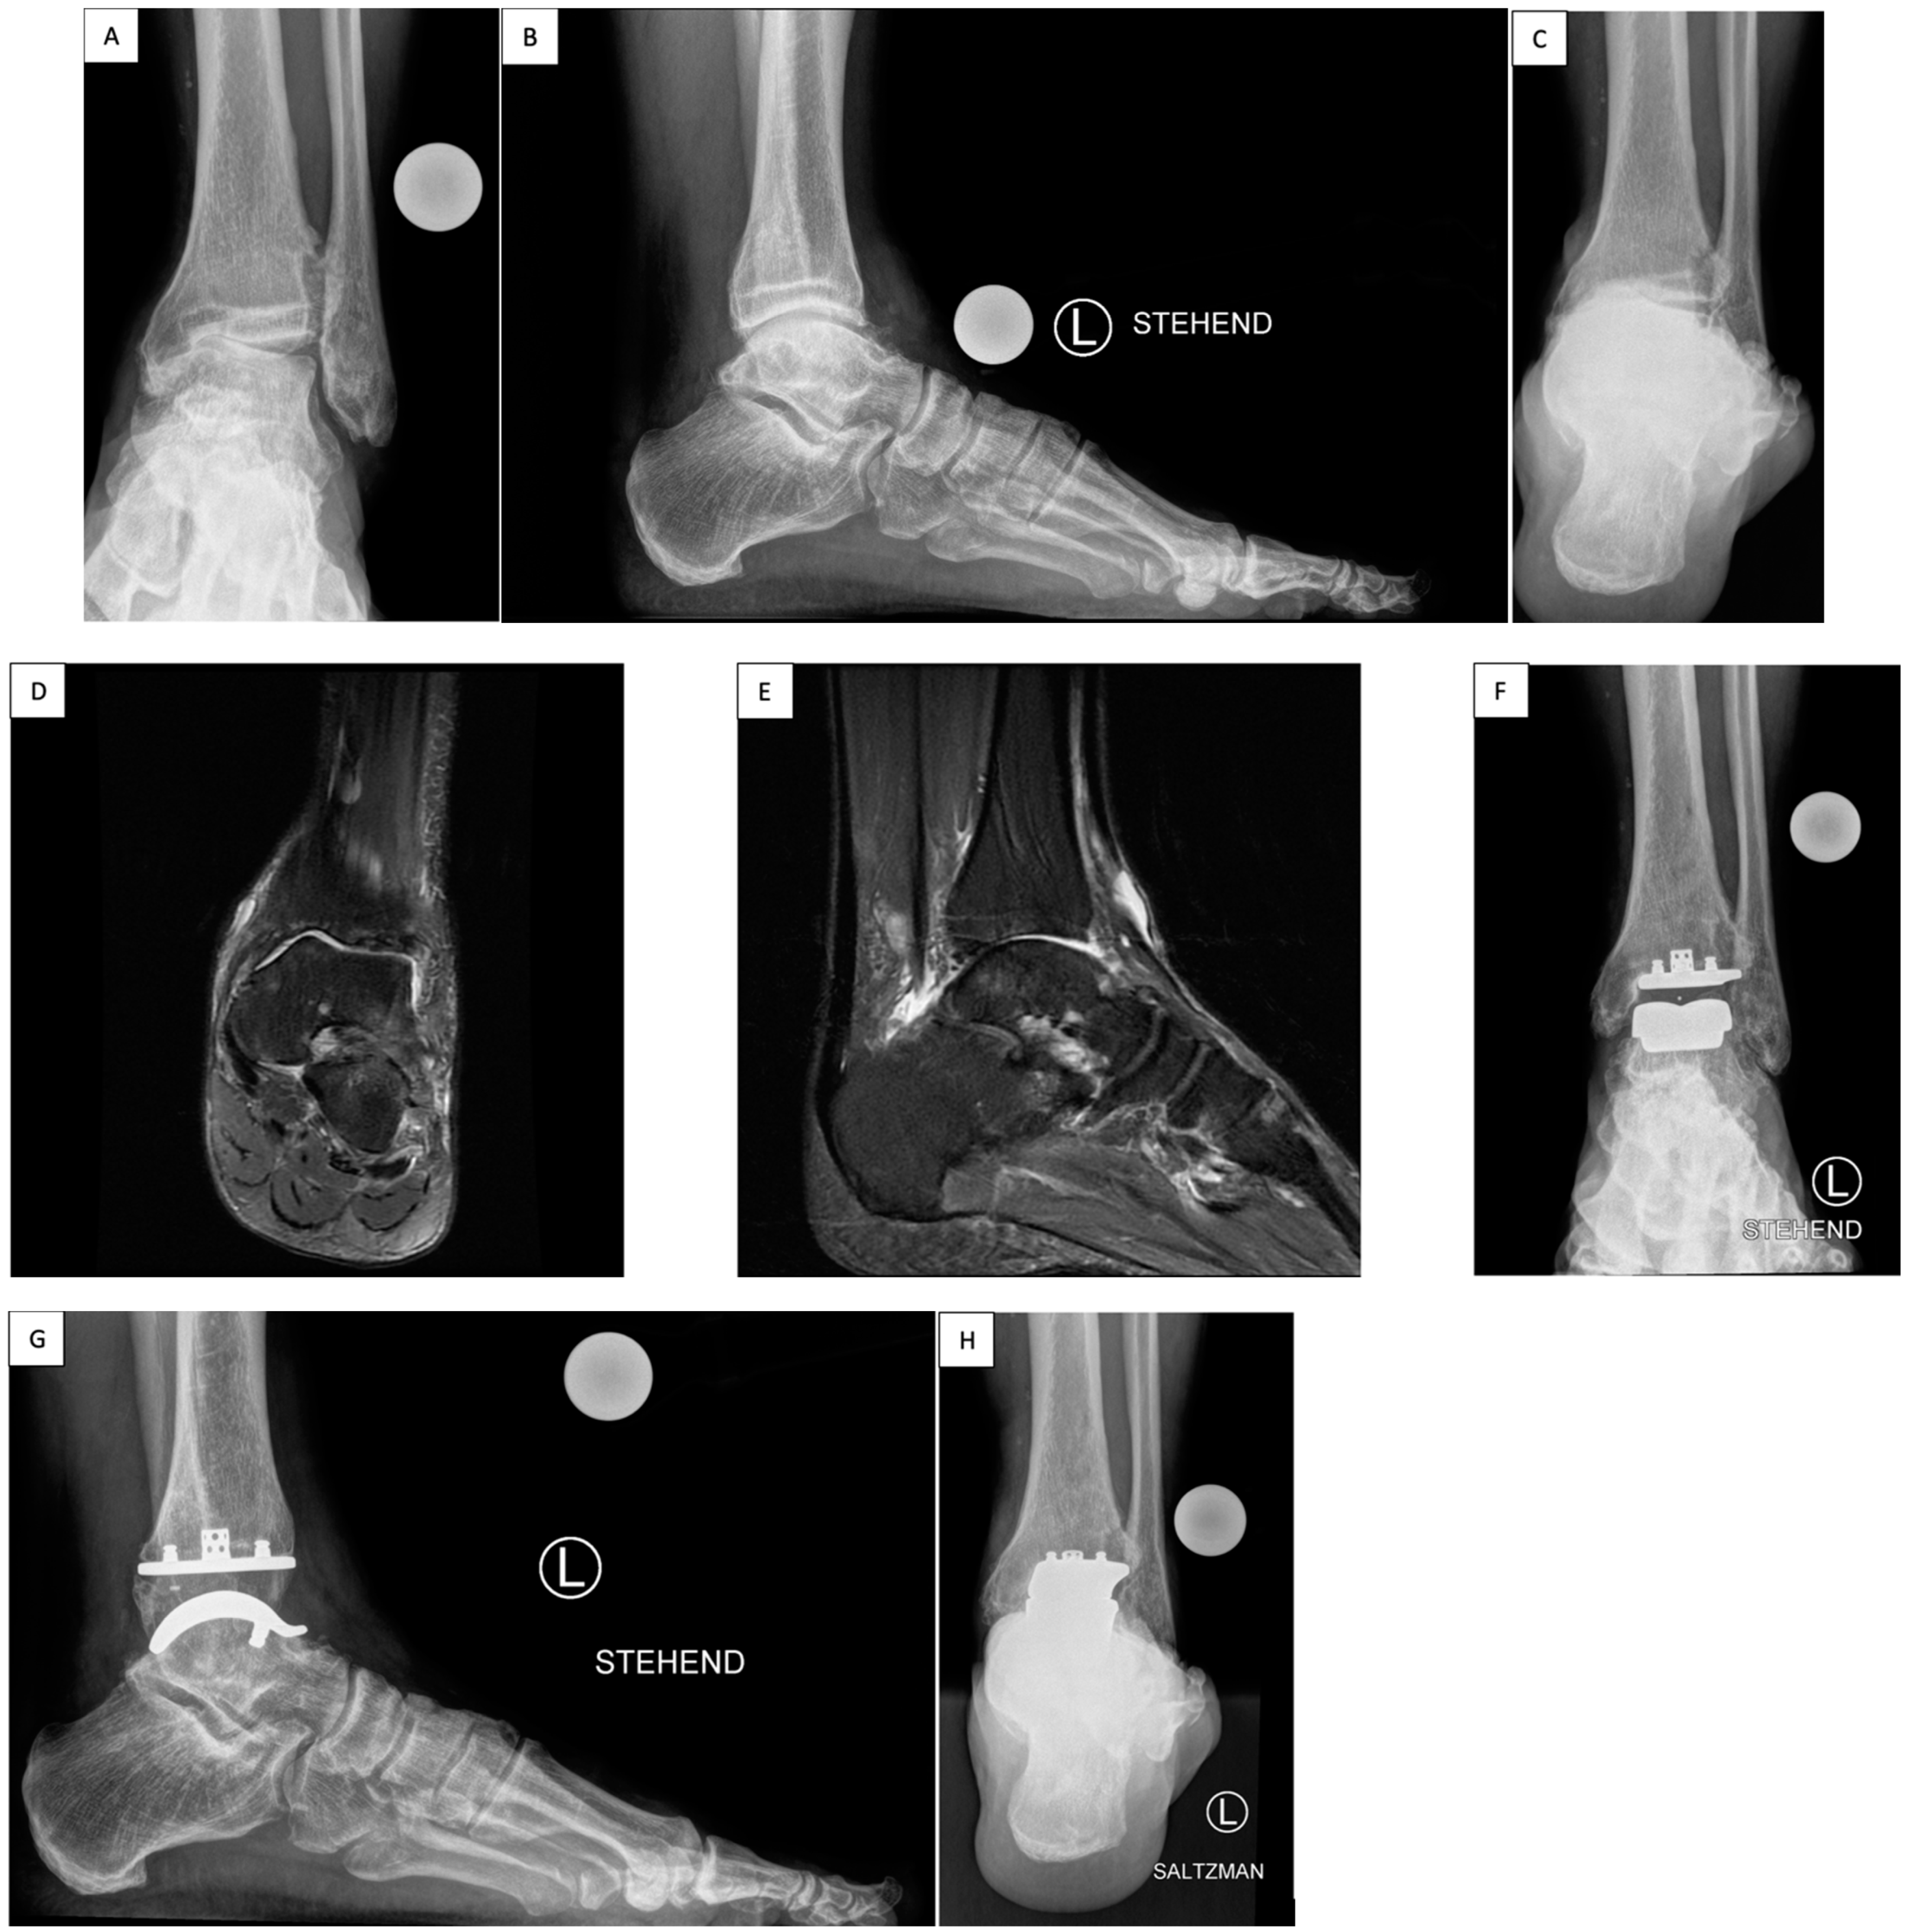

2.1. Surgical Technique